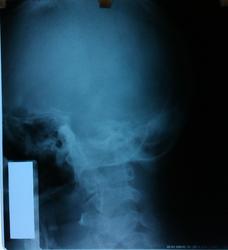

Пол пациента: Мужской пол Тип патологии: Другое Область исследования: Череп и головной мозг Методы исследования: Rg Пациент. 54 г. с диагнозом неврит лицевого нерва. Как описать РГ в данном случае подскажите, пожалуйста? https://radiomed.ru/sites/default/files/styles/case_slider_image/public/user/18609/img_20130920_112024.jpg?itok=h__x4C1e ID:31943 Пт, 20/09/2013 - 23:27 #1 Андрей Юрьевич Не на сайте Был на сайте: 6 дней 10 часов назад Зарегистрирован: 16.11.2008 - 22:16 Публикации: 18098 Конфигурация верхушек пирамид височных костей анатомически правильные, р-признаков деструкции не выявлено, просветы внутренних слуховых проходов не расширены. Андрей Юрьевич Сб, 21/09/2013 - 13:45 #2 И.Бондаренко Не на сайте Был на сайте: 2 дня 4 часа назад Зарегистрирован: 13.09.2011 - 22:55 Публикации: 9206 Укладка по Стенверсу (височные кости)? Обычно описываем слуховые проходы. Их просвет должен быть одинаков. Пнд, 23/09/2013 - 09:37 #3 Dr. GreenThumb Не на сайте Был на сайте: 2 года 2 месяцев назад Зарегистрирован: 29.05.2010 - 10:16 Публикации: 239 Оценивают стенки внутренних слуховых проходов, строение пирамид, и наличие/отсутствие деструктивных изменений. Обычно назначают неврологи на предмет опухолей. The time has come, the rules have changed... Пнд, 23/09/2013 - 15:00 #4 Dr. X-ray Не на сайте Был на сайте: 9 лет 6 месяцев назад Зарегистрирован: 19.07.2013 - 21:06 Публикации: 505 спасибо большое за ответы.

Конфигурация верхушек пирамид височных костей анатомически правильные, р-признаков деструкции не выявлено, просветы внутренних слуховых проходов не расширены.

Укладка по Стенверсу (височные кости)? Обычно описываем слуховые проходы. Их просвет должен быть одинаков.

Оценивают стенки внутренних слуховых проходов, строение пирамид, и наличие/отсутствие деструктивных изменений. Обычно назначают неврологи на предмет опухолей.